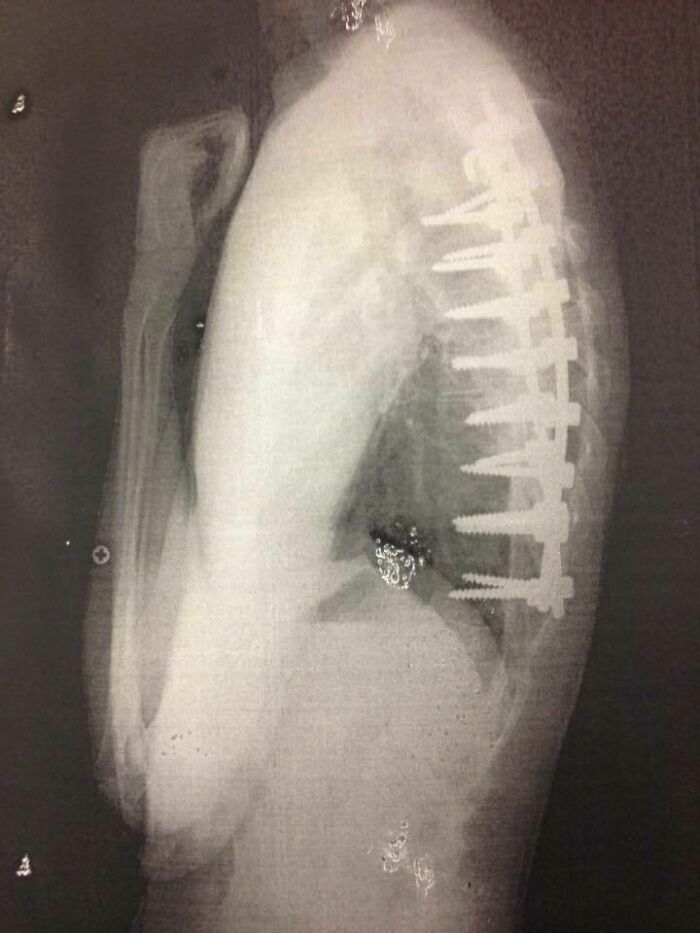

Before & After A Total Spinal Fusion

In My Head, The Screws From My Spinal Fusion Surgery Looked A Lot Smaller

Have my own set of these. Can agree this is what they look like on xray